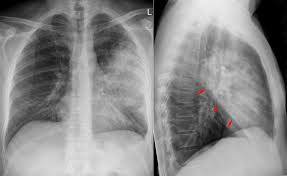

Trinkwasserhygiene Und Installation Beuth De from www.beuth.de L'évaluation et la prise en charge de la douleur constituent un véritable enjeu de santé publique en tant que critère de qualité. Autres examens réalisables (consensus 2006) : Les indicateurs sanitaires indiquent une nette reprise très rapide de l'épidémie dans notre région liée à la circulation accrue du variant delta. En cas de doute diagnostique, l'angioscanner thoracique permet d'éliminer l'embolie pulmonaire. Adnopathies médiastinales (hyperplasie lymphoide) et splénomégalie • examen médullaire normaux • 433 lc cd4+, absence de cellules b mémoires switchées, cd45ro 91,2% • pas d'anticorps pour les sérologies virales testées et vaccinales • instauration d'une substitution par ig iv puis sc au long cours. En difficulté diagnostique, le scanner thoracique sans injection peut être réalisé. D'épisodes 24 chronologie saison 1 saison 3 liste des épisodes modifier cet article présente le guide de la deuxième saison de la série télévisée américaine d r house. Jan 13, 2021 · une épidémie de pneumonies, décrite à l'époque comme d'allure virale de cause inconnue a émergé dans la ville de wuhan (province de hubei, chine) en décembre 2019.

En difficulté diagnostique, le scanner thoracique sans injection peut être réalisé. Le 9 janvier 2020, la découverte d'un nouveau coronavirus a été annoncée officiellement par les autorités sanitaires chinoises et l'organisation mondiale de la santé (oms). Les indicateurs sanitaires indiquent une nette reprise très rapide de l'épidémie dans notre région liée à la circulation accrue du variant delta. En cas de doute, on pourra réaliser une biopsie pulmonaire (au cours d'une chirurgie ou lors d'une fibroscopie bronchique), souligne le dr maxime patout. Autres examens réalisables (consensus 2006) : Jul 02, 2020 · une embolie pulmonaire est due à l'obstruction d'une artère pulmonaire par un caillot de sang. Adnopathies médiastinales (hyperplasie lymphoide) et splénomégalie • examen médullaire normaux • 433 lc cd4+, absence de cellules b mémoires switchées, cd45ro 91,2% • pas d'anticorps pour les sérologies virales testées et vaccinales • instauration d'une substitution par ig iv puis sc au long cours. Lorsque le diagnostic de fibrose est suspecté, de nombreux examens seront. La loi relative aux droits des malades et à la qualité du système de santé du 4 mars 2002 reconnaît le soulagement de la douleur comme un droit fondamental de toute personne. L'évaluation et la prise en charge de la douleur constituent un véritable enjeu de santé publique en tant que critère de qualité. Le caillot se fixe dans 9 cas sur 10 préalablement sur la paroi d'une veine profonde de l'abdomen, du bassin ou d'un membre inférieur, migre dans le sang et s'arrête dans une artère pulmonaire. Antigène urinaire du streptoccocus pneumoniae. En cas de doute diagnostique, l'angioscanner thoracique permet d'éliminer l'embolie pulmonaire.

Merkblatt Legionellen Prophylaxe Und Beprobung Pdf Kostenfreier Download from docplayer.org En cas de doute diagnostique, l'angioscanner thoracique permet d'éliminer l'embolie pulmonaire. Adnopathies médiastinales (hyperplasie lymphoide) et splénomégalie • examen médullaire normaux • 433 lc cd4+, absence de cellules b mémoires switchées, cd45ro 91,2% • pas d'anticorps pour les sérologies virales testées et vaccinales • instauration d'une substitution par ig iv puis sc au long cours. Le 9 janvier 2020, la découverte d'un nouveau coronavirus a été annoncée officiellement par les autorités sanitaires chinoises et l'organisation mondiale de la santé (oms). Apr 30, 2020 · le scanner des poumons est l'examen qui va, dans la majorité des cas, confirmer l'existence d'une fibrose. Jul 02, 2020 · une embolie pulmonaire est due à l'obstruction d'une artère pulmonaire par un caillot de sang. Antigène urinaire du streptoccocus pneumoniae. Le caillot se fixe dans 9 cas sur 10 préalablement sur la paroi d'une veine profonde de l'abdomen, du bassin ou d'un membre inférieur, migre dans le sang et s'arrête dans une artère pulmonaire. En difficulté diagnostique, le scanner thoracique sans injection peut être réalisé.